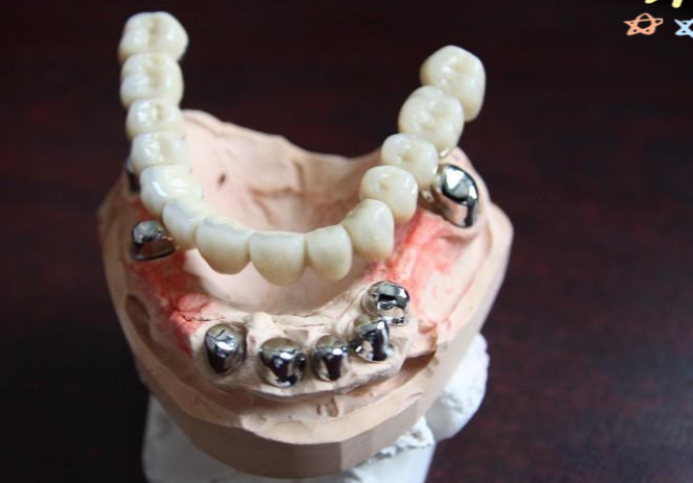

套筒冠义齿收费标准受材料选择、修复范围、医疗机构类型等多种因素影响,不同地区的收费差异明显。www.59w.net目前市场上,单颗套筒冠义齿价格从4500元起,全口套筒冠无挂钩假牙34000元起,具体费用需结合患者口腔条件、所选材料及机构报价较终确定。

总的来说,套筒冠义齿收费标准区间较大,单套价格从3800元起,全口价格34000元起,半口价格18000元起。具体费用会因材料选择、修复范围、附加治疗及机构差异而变化。建议患者根据自己的口腔条件和预算,选择正规的口腔机构,面诊后确定适合的方案,不要只看价格而忽略修复疗效和长期稳定性。